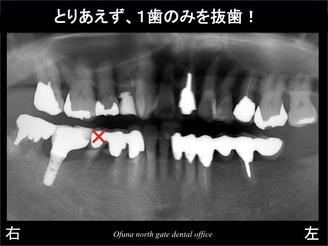

以下が初診時になります。

右下の奥歯の被せ物が取れたとのことで来院されました。

診査の結果、

虫歯が深く、

歯根破折 も起こしていました。

上記のレントゲン写真の丸で囲んだ部分を拡大したのが 以下になります。

とりあえず、奥の1歯のみ抜歯します。